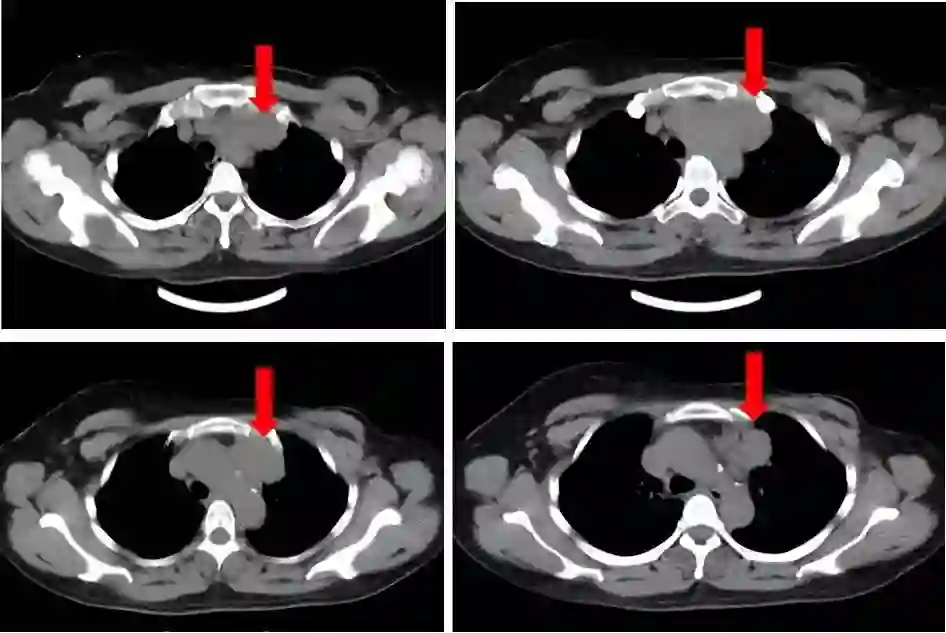

2017年1月12日门诊复查。左锁骨上窝可触及一大小约2.0×2.0cm肿大淋巴结,质略硬,活动度差。左颈部浅静脉怒张、左胸壁浅静脉曲张。右乳未触及肿物,双侧腋窝未触及肿大淋巴结。门诊彩超示:左侧锁骨上窝探及多个低回声结节,大的2.0*0.9cm,边界清楚,形态规整,皮髓分辨不清,诊断为左侧锁骨上窝多发肿大淋巴结。入院进一步复查,肺、脑、骨、肝未见远处转移征象。循环肿瘤细胞数0个/7.5mL外周血。2017年1月12日行胸部CT平扫示:前上纵隔左侧见一软组织密度影,部分边界欠清,最大截面约7.2cm×2.9cm。

图1. 胸部CT平扫